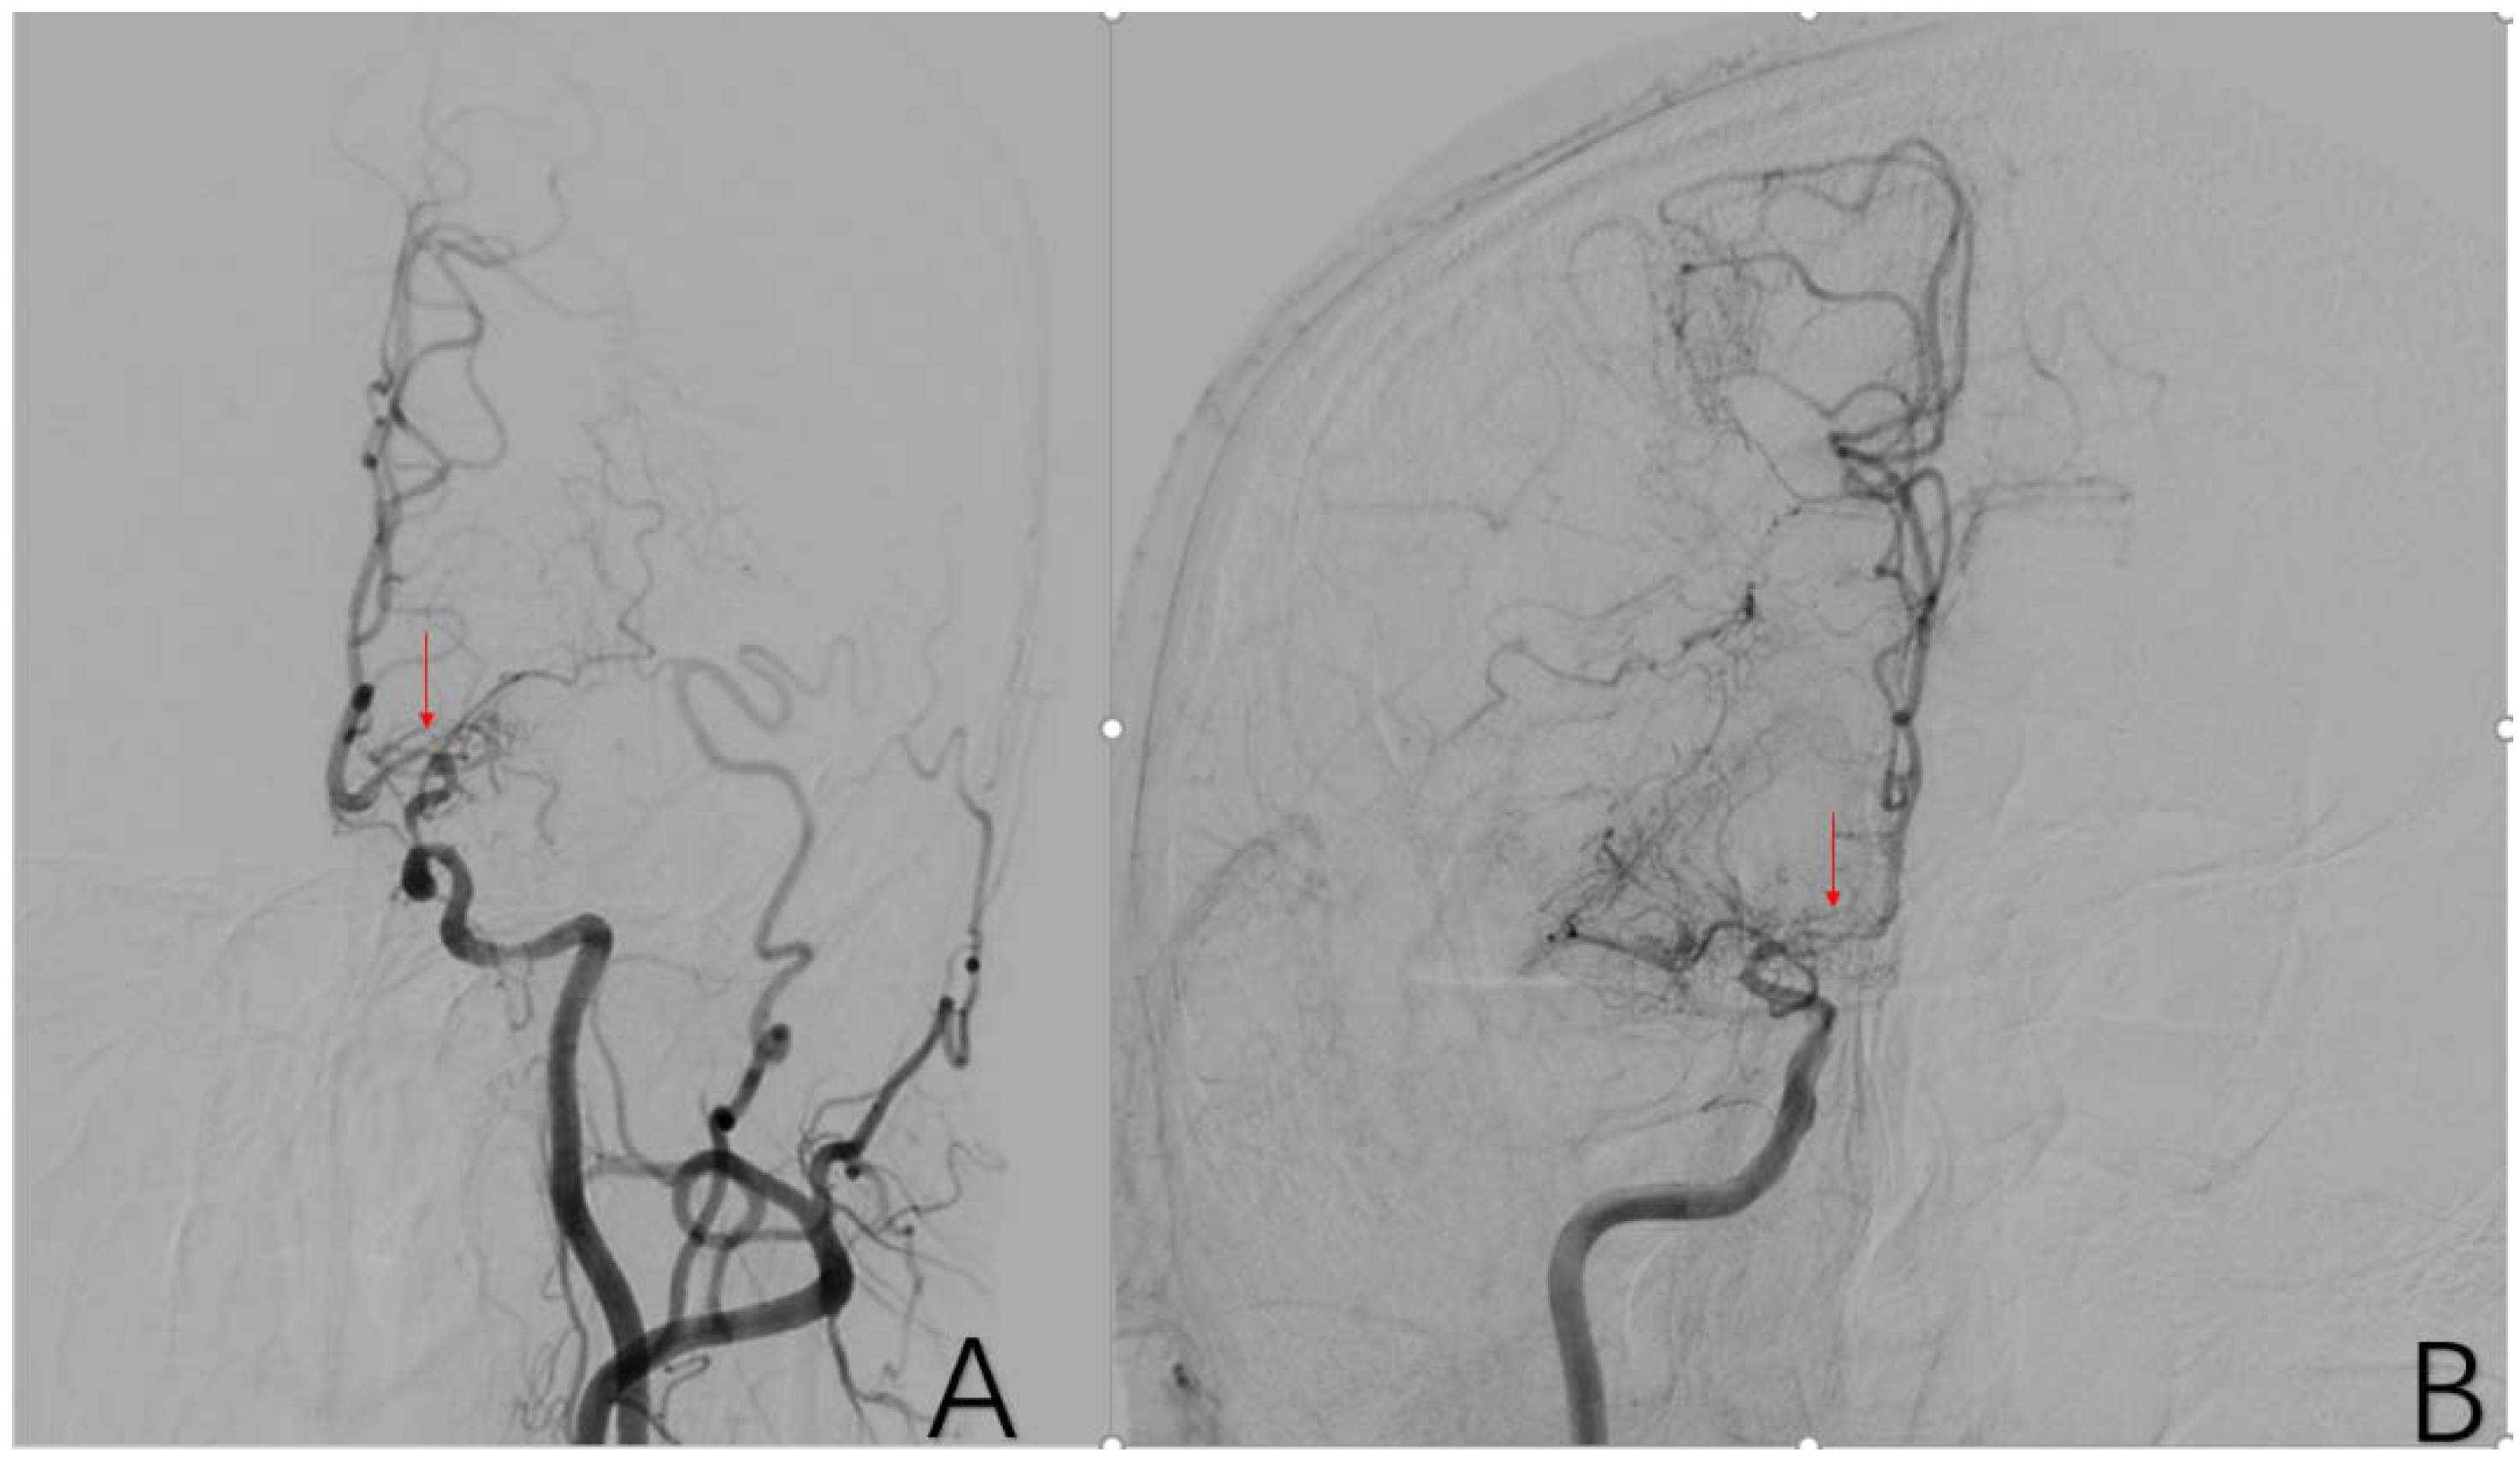

2.3.11. Factor 6 Unstable Compensation

2.3.10. Factor 5 Posterior Circulation Compensation

2.3.9. Factor 4 PCA Anomaly